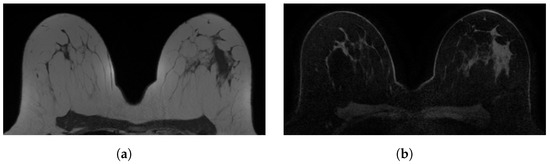

Figure 1. Examples of in-phase and reconstructed water Dixon acquisitions from our internal dataset used to mimic acquisitions without (WOFS) and with (FS) fat suppression. (a) In-phase Dixon acquisition used as WOFS image. (b) Reconstructed water Dixon acquisition used as FS image.

2. Materials and Methods